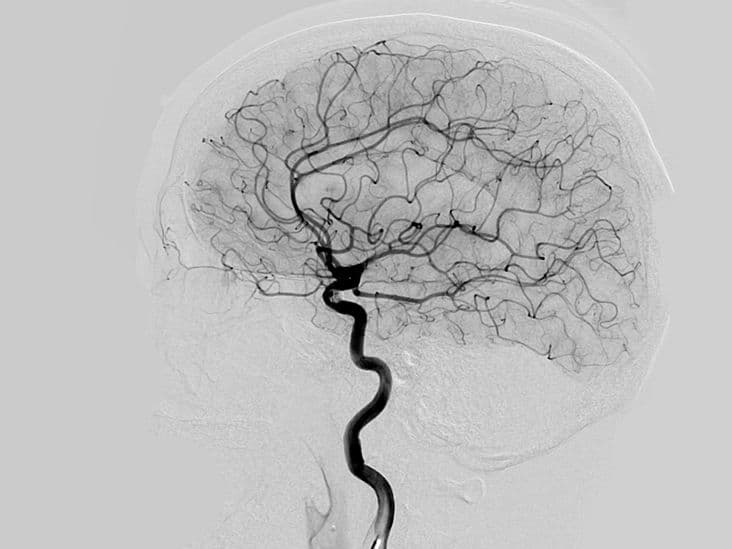

There are different types of angiographies, each tailored to specific diagnostic needs. Coronary angiography, for instance, is used to examine the arteries supplying blood to the heart, helping to diagnose coronary artery disease and guide interventions such as angioplasty or stenting. Cerebral angiography focuses on the blood vessels in the brain, aiding in the detection of aneurysms, arteriovenous malformations, or blockages that could lead to stroke. Pulmonary angiography examines the blood vessels in the lungs, often used to diagnose conditions like pulmonary embolism.

Individuals with chronic kidney disease or those on hemodialysis may need angiography to assess the blood vessels used for dialysis access. Ensuring these vessels are functioning properly is vital for effective dialysis treatment. Additionally, patients with unexplained episodes of fainting, dizziness, or stroke-like symptoms may undergo cerebral angiography to evaluate blood flow to the brain and identify potential blockages or abnormalities.